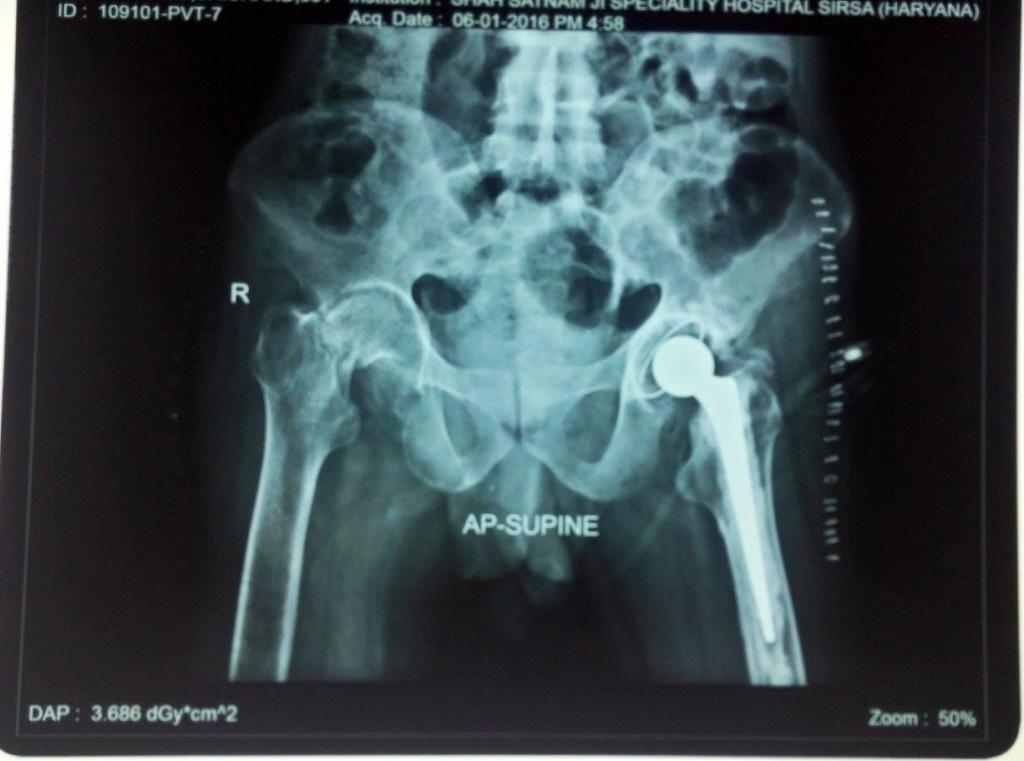

Hip replacement, medically termed hip arthroplasty, is a sophisticated surgical procedure meticulously designed to alleviate debilitating pain and restore functional independence in individuals afflicted by a damaged or severely arthritic hip joint. This transformative intervention becomes imperative when non-surgical remedies prove inadequate in mitigating pain and improving mobility. A comprehensive preoperative assessment is conducted, encompassing a meticulous review of the patient's medical history, a thorough physical examination, and the analysis of diagnostic imaging such as X-rays and MRIs. These evaluations serve to gauge both the patient's overall health and the extent of hip joint deterioration, helping the orthopedic surgeon determine the appropriateness of hip replacement.

The surgical process commences with a carefully placed incision over the hip joint, which provides access to the compromised joint. The length and location of the incision depend on the chosen surgical approach. Once access is gained, the damaged or arthritic bone and cartilage within the hip joint are meticulously removed, creating space for the insertion of artificial hip components. These prosthetic components, including the femoral stem, acetabular cup, and other specialized parts, are precisely positioned and securely fixed within the joint. These components can be constructed from various materials, such as metal, ceramic, or high-density polyethylene, depending on the individual patient's needs and circumstances.

In addition to the clinical evaluation, diagnostic imaging studies such as X-rays and MRIs are often performed. X-rays provide detailed images of the hip joint, allowing the surgeon to assess the extent of joint degeneration, bone damage, and alignment issues. MRIs offer a more comprehensive view of the soft tissues surrounding the hip joint, helping to identify conditions like cartilage damage or labral tears. Collectively, this comprehensive evaluation guides the surgeon in making an informed decision regarding the necessity and appropriateness of hip replacement surgery for the patient, taking into account their overall health and the severity of hip joint issues.

Implant placement is a crucial phase in the hip replacement surgery, where the artificial hip components are meticulously positioned and securely fixed within the joint. These components typically consist of the femoral stem, acetabular cup, and any associated parts, each carefully chosen to match the patient's unique needs and anatomy.

The surgeon's skill and precision are paramount during this step, as the proper alignment and placement of these components are essential for the success of the procedure. The femoral stem, typically made of metal, is inserted into the hollowed femur to provide stability and support. The acetabular cup, which can be composed of materials like ceramic or high-density polyethylene, is implanted in the hip socket to recreate a smooth, low-friction joint surface.

The choice of implant materials may vary based on the patient's specific needs and the surgeon's expertise. These materials are selected for their durability and compatibility with the patient's lifestyle, aiming for long-lasting pain relief and improved joint function.

Once the artificial components are securely in place, they mimic the natural hip joint's structure and function, offering patients the potential for renewed mobility and a significant reduction in pain. The success of implant placement significantly contributes to the overall effectiveness of hip replacement surgery.